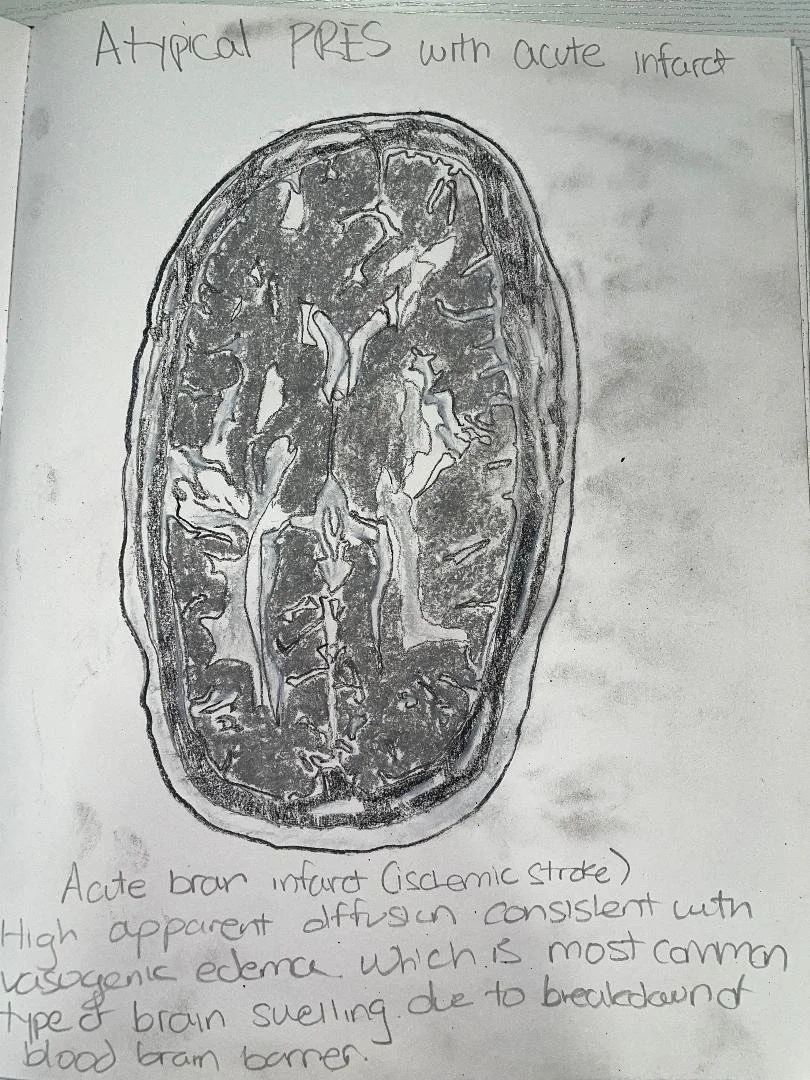

Atypical PRES with acute infarct